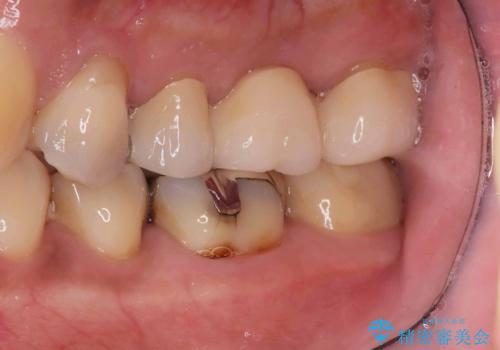

- 銀歯2本の下が虫歯になっていたので、フルジルコニアクラウンとセラミックインレーで治療を行いました。

適合が良い被せ物を入れるために、歯の境としっかり合わせた仮歯を入れ、歯茎の状態を良くしてからシリコンで型取りをしています。